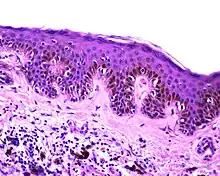

Melanocytic nevus

Lentiginous melanocytic naevus